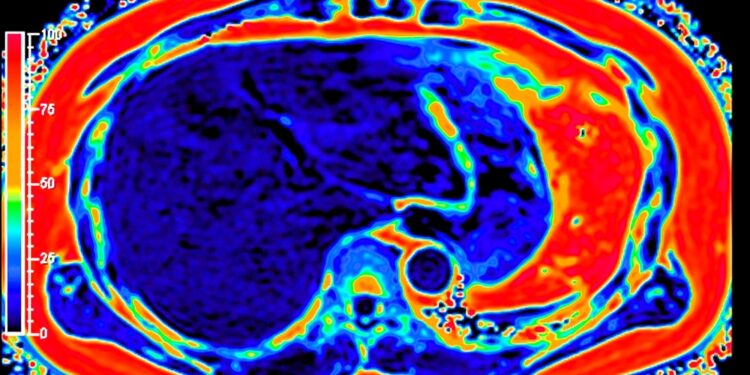

- Vaizdiniai tyrimai: naudojami kompiuterinės tomografijos (KT), magnetinio rezonanso (MRT) ar pozitronų emisijos tomografijos (PET) tyrimai. Jie padeda įvertinti, kiek liga išplito.